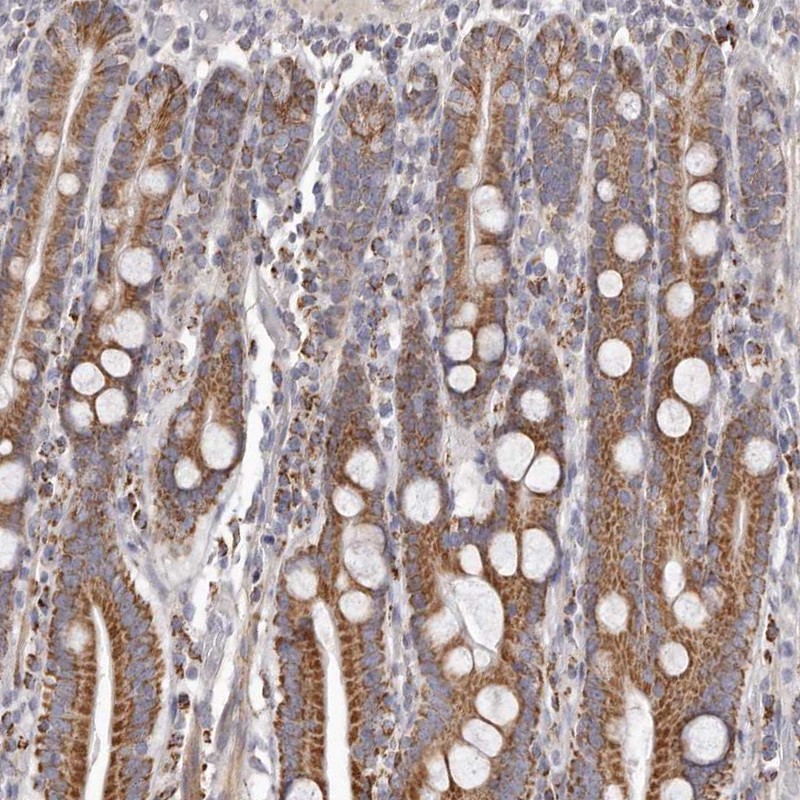

Immunohistochemical staining of human duodenum shows strong cytoplasmic positivity in glandular cells.